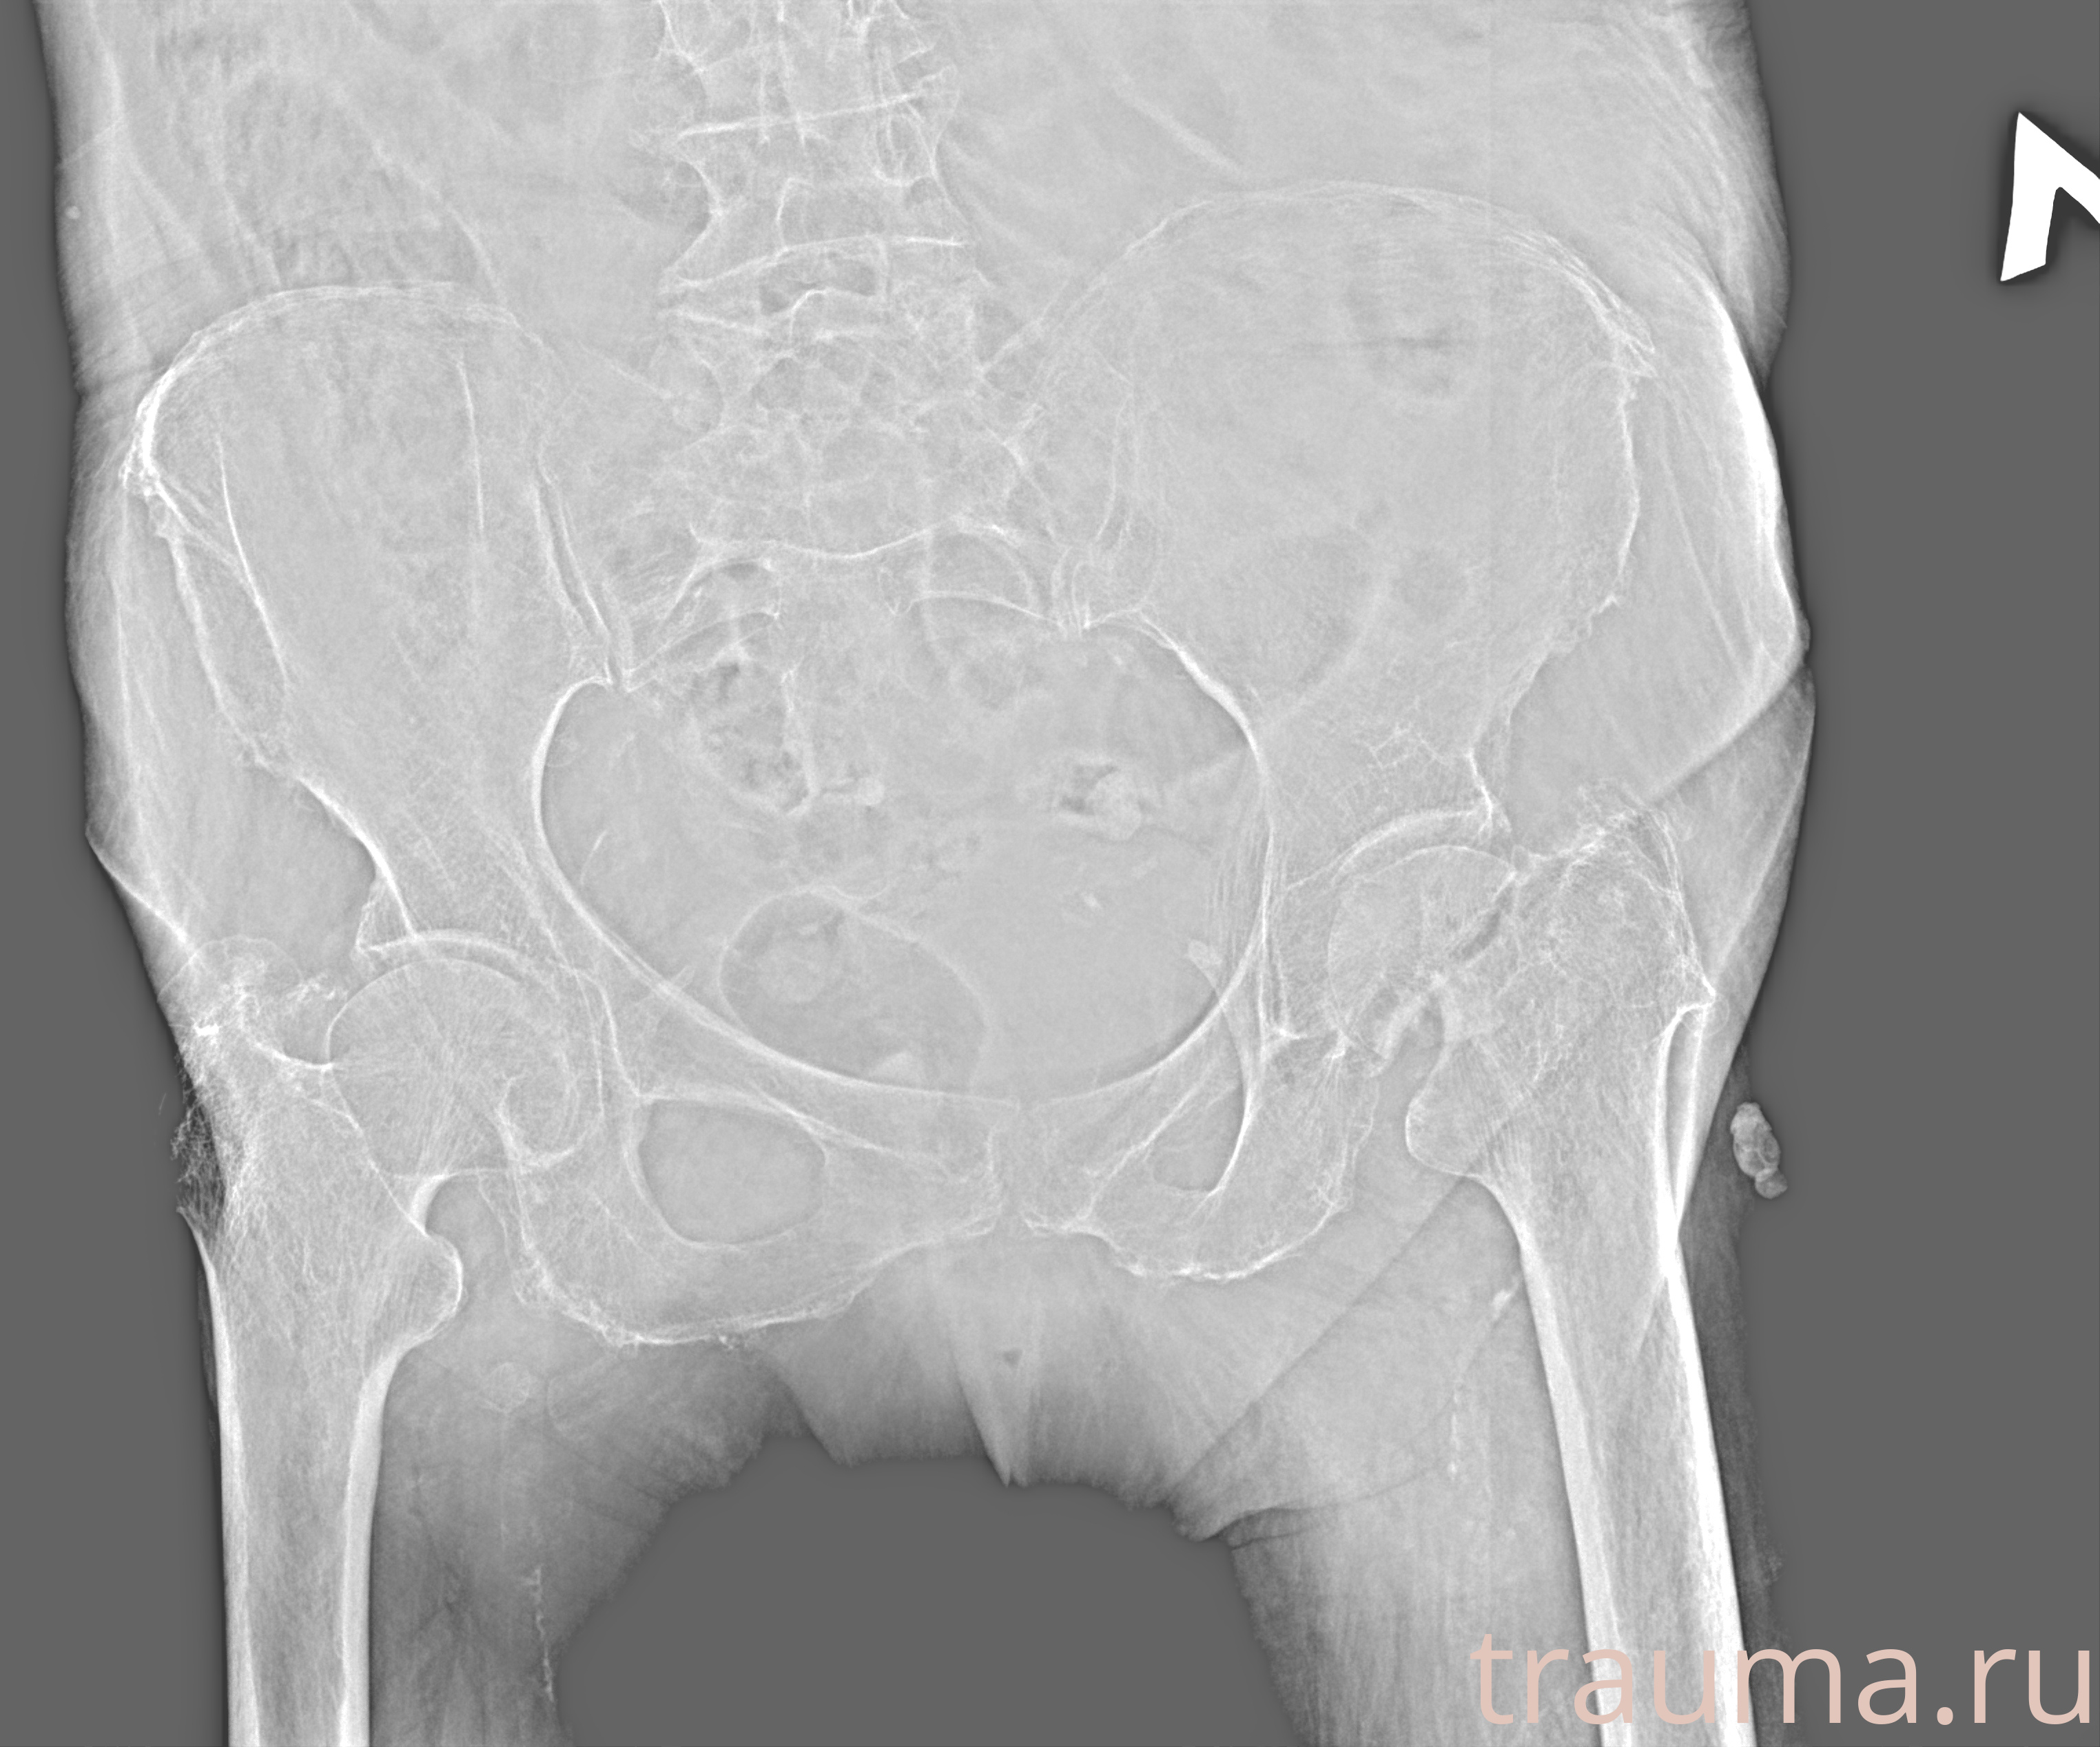

Рентген на дому: по вашему адресу приезжает врач-рентгенолог, травматолог-ортопед с мобильным рентгеновским аппаратом, проводит диагностику травмы или заболевания, делает необходимые рентгенограммы, дает рекомендации по дальнейшему лечению. Получить качественные снимки в домашних условиях возможно благодаря уникальной методике, разработанной МосРентген Центром для института  Склифосовского